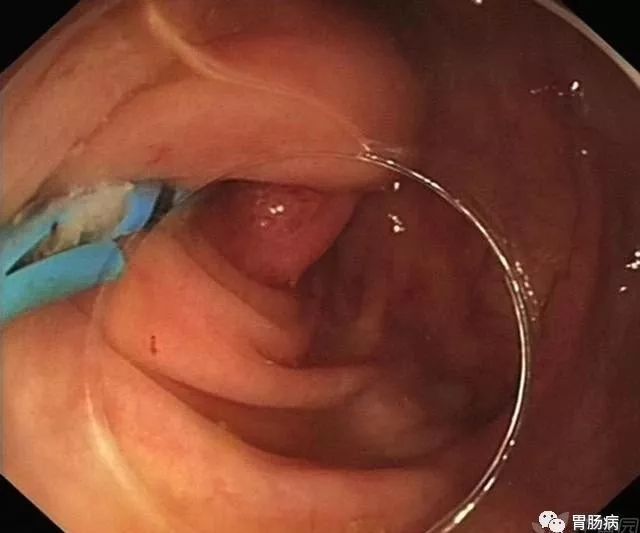

充分的肠道准备会有效减少ERAT操作时间,正常的阑尾开口部都被Gerlach’s瓣覆盖(如图,双箭头示Gerlach’s瓣);会造成插管困难,加上特制的锥形透明帽后插管就变得相对容易。

通过内镜前端的透明帽的帮助下,推开Gerlach’s瓣,并进行阑尾腔插管。